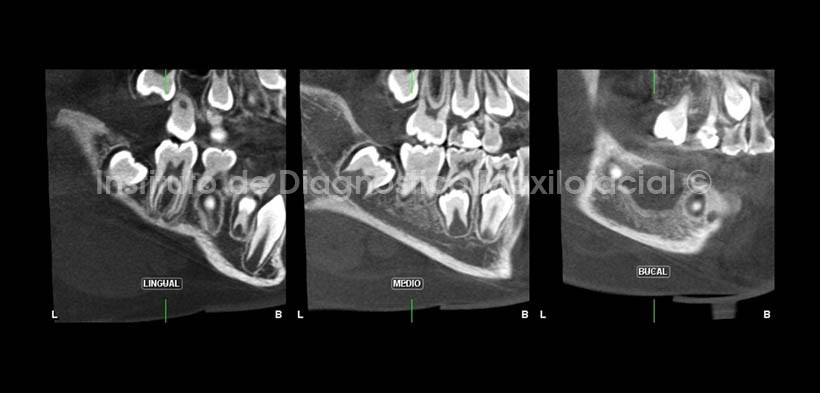

En la evaluación con tomografía cone beam, se observa en cortes tangenciales y a nivel del corte bucal o vestibular, la presencia de una imagen radiolúcida de limites definidos, rodeada por el aumento de la densidad ósea circundante sugiriendo la presencia una lesión quística de origen odontogénica, compatible con Quiste Bucal Mandibular Infectado.

En cortes axiales y coronales (Fig.3 y 4), se observa el considerable aumento de volumen en el lado afectado, asi como el aumento de la densidad osea circundante ya mencionado y el adelgazamiento de la tabla osea vestibular a nivel del tercio cervical radicular (mas evidente en cortes axiales). Asi mismo, se observa la relación de la lesion con el germen dentario de la pieza 3.7.

La atenuación o la pérdida de la lámina dura alrededor de los ápices y en zona de furcación del diente afectado son signos radiográficos de esta lesión, presentando una zona radiolúcida de forma redondeada y limites definidos asociada al diente afectado. Así mismo, cuando la infección afecta el periostio, se observa radiográficamente la reacción del mismo como el aspecto de capas de cebolla, observándose con mayor claridad en incidencias oclusales y en tomográfia cone beam, sin embargo en la radiografía panorámica es posible evidenciar estos signos en relación con la basal mandibular. En estadios más avanzados se observa la considerable expansión del cuerpo mandibular conformada por zonas de aumento de la densidad ósea.